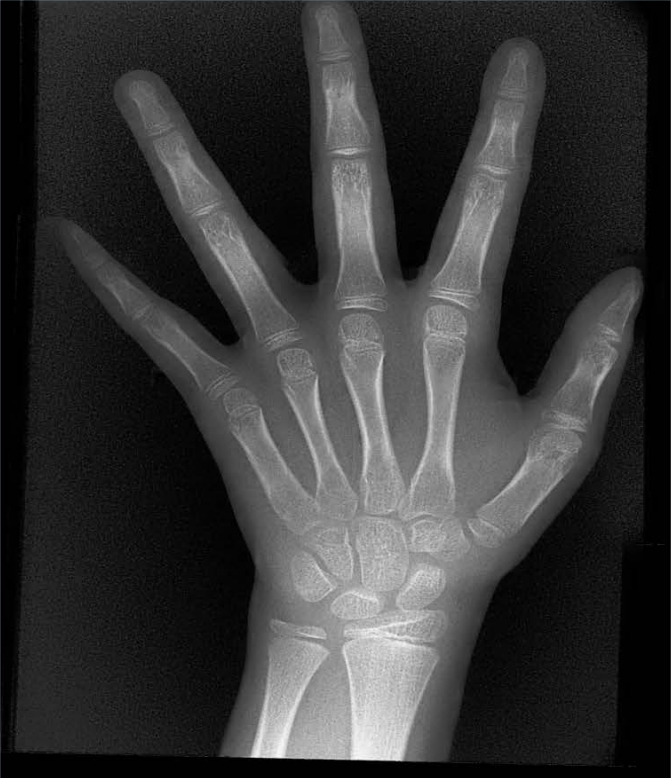

骨齡是反映兒童真實生長發育水平的關鍵指標,為相關疾病診療提供重要支撐。它可助力身高異常疾病病因診斷,支撐矮小癥等治療的監護與療效評估,還能精準評估生長發育及青春期突增狀況,為早期干預提供依據。

X射線骨齡儀適用于兒童保健科、內分泌科、兒科等多個臨床科室,可滿足不同年齡段兒童的骨齡檢測需求。無論是常規生長發育評估、身高異常篩查,還是疾病治療后的療效監測,其檢測結果都能為臨床診療提供標準化、可對比的科學數據,助力醫療機構提升診療規范化水平。